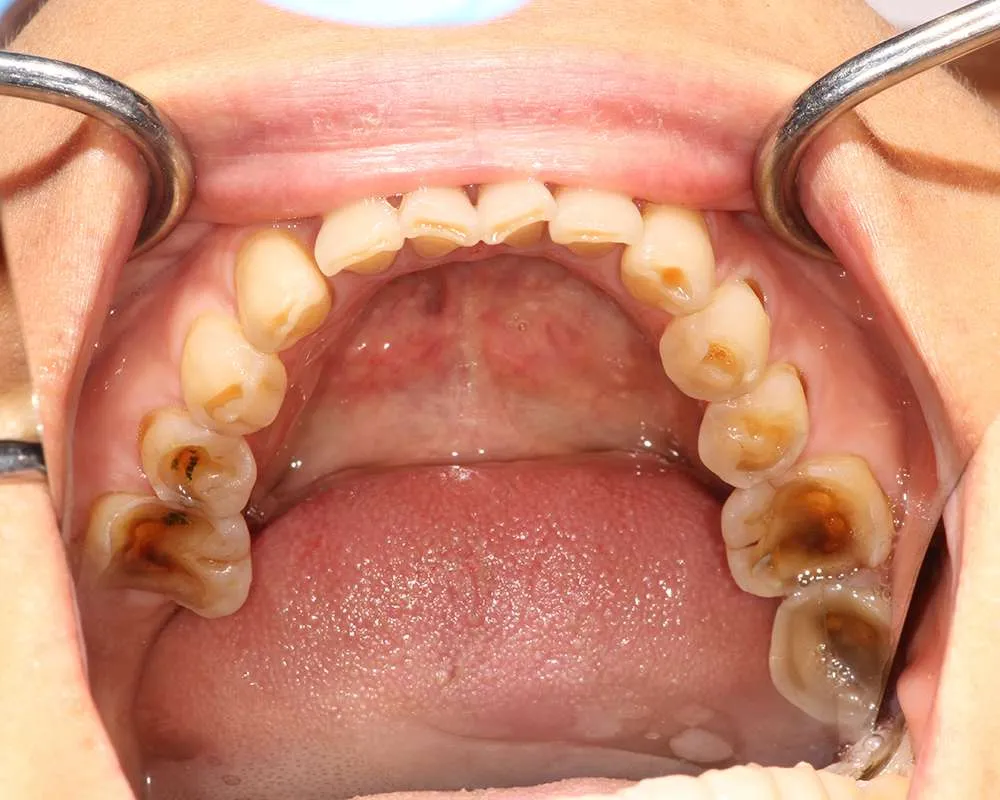

Real Stories, Real Results: Case Studies Showcasing How Our Personalized Approach Transforms Smiles and Lives

Complex Cases

Witness the Remarkable Changes We Can Achieve